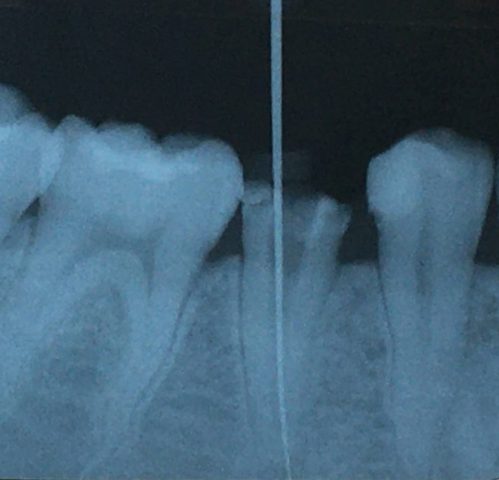

フィステルとは歯ぐきにできるニキビのようなものです。「サイナストラクト」、「瘻孔(ろうこう)」、「内歯瘻(ないしろう)」などと呼ばれることもあります。重度のむし歯などで神経が死に治療をせずに放っておくと慢性的な炎症になり、やがて根っこの尖端に膿が溜まります。その膿を排出するための出口としてできたものがフィステルの正体です。

膿が溜まりに溜まると膜が破れて膿を排出します。そして膿を出し終わるといったん消失し、また膿が溜まるとフィステルができます。この繰り返しです。つまり根本の原因を取り除かないことにはフィステルは自然治癒しません。

1.根管治療

歯の根っこの治療です。針のような器具をつかい、細菌や細菌に感染した神経を除去し、根管内(神経の入っている管)を清掃・消毒します。根管治療は歯冠部(歯ぐきから上にでている部分)からアプローチします。これにより根っこの炎症がおさまればフィステルは消失します。